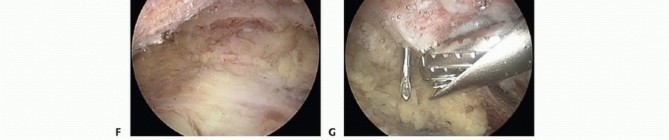

The electrocautery device is used to peel the coracoacromial ligament from the undersurface of the acromion and completely excise the remaining ligament stump. A complete resection of the coracoacromial ligament is confirmed when the undersurface of the deltoid is visualized as it drapes over the acromial edge(TECH FIG 2C). Anterior acromioplasty is performed with a 5.5-mm burr via the lateral portal. Resection begins in the anterolateral corner of the acromion. The desired depth of resection, estimated from the preoperative films, is obtained by measuring with the diameter of the burr(TECH FIG 2D).

TECH FIG 2 • A. Arthroscopic bursectomy. The bursa overlying the tendinous portion of the rotator cuff must be thoroughly resected to evaluate the tendons for bursal-side rotator cuff tear. B. Soft tissue on the undersurface of the acromion is denuded with a radiofrequency electrocautery. Removing the soft tissue will expose the bony undersurface of the acromion and facilitate acromioplasty by the burr's cutting flutes. C. The acromial spur is now completely visualized. The coracoacromial (CA) ligament must be completely resected from the anterolateral acromion. Failure to do so may result in residual impingement by the CA ligament. Visualization of the undersurface fibers of the deltoid indicates a complete CA ligament resection. D. The acromioplasty begins at the far anterolateral tip of the acromion. The burr's diameter, usually 5 to 6 mm, is used to assess the initial depth of the acromial resection. The acromioplasty proceeds in 5- to 6-mm strips from anterior to posterior and lateral to medial. E. Completed acromioplasty. The undersurface of the acromion is converted to a type I morphology. Any residual ridges or rough edges can be safely smoothed with the burr in the reverse cutting position. F. View of the acromioplasty from the lateral portal. At the procedure's completion, the arthroscope should be placed in the lateral portal to assess the acromion for any residual downslope or unresected bone. The AC joint is also well visualized from this portal and may be resected or coplaned via the anterior portal. G. Coplaning of the AC joint. The posterior or lateral portal is used for arthroscopic visualization. Coplaning is performed with the burr in the anterior or lateral portal. This depth of resection is achieved anteriorly from the anterolateral corner of the acromion to the medial acromial facet of the AC joint. The depth of resection is then progressively thinned posteriorly to the midportion of the acromion such that there is a smooth zone of transition from the anterior to the midportion of the acromion(TECH FIG 2E).

Any ridges or rough edges may be smoothed with the burr in the “reverse cutting” position. The reverse position provides a much less aggressive bone resection, which is ideal for smoothing the soft cancellous undersurface exposed following acromioplasty. The arthroscope is placed in the lateral portal to check the adequacy of resection(TECH FIG 2F). Any residual unresected acromion or impinging osteophytes from the undersurface of the AC joint should be resected. Radiofrequency electrocautery should be used to resect the highly vascular soft tissue on the undersurface of the AC joint. From the anterior or lateral portal, the 5.5-mm burr is used to coplane the distal portion of the clavicle flush with the acromion(TECH FIG 2G).